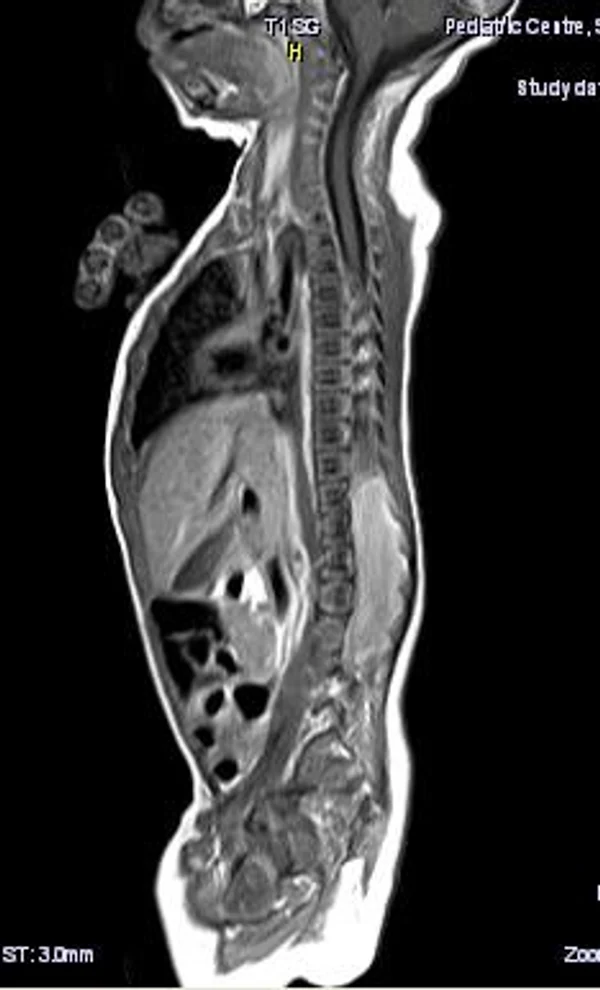

В качестве примера приведены 2 случая хирургического лечения новорожденных с врожденными опухолями головного мозга и позвоночного канала. У новорожденной девочки опухоль (хориодпапиллома) располагалась в области треугольника правого бокового желудочка (рис. 28 а, б). В возрасте 2-х недель жизни опухоль удалена. По данным МРТ головы с внутривенным введением контрастного препарата выполненной через 2 дня после операции опухоль удалена тотально (рис. 28 в). Послеоперационных осложнений не наблюдалось. У второго пациента 2-х нед. жизни врождённая опухоль (нейробластома) располагалась в позвоночном канале на уровне Th10-L3 позвонков (рис. 29 а) и распространялась в забрюшинное пространство. Клиническая картина заболевания складывалась из нижнего вялого парапареза и нарушения функции тазовых органов. Во время операции остистые отростки Th 11-L3 позвонков рассечены по средней линии. Дужки 6 данных позвонков надломлены и разведены в стороны. Опухоль располагалась экстрадурально, отделена от дорзальной поверхности дурального мешка и корешков спинно-мозговых нервов, после чего полностью удалена из позвоночного канала. Половинки дужек позвонков сведены к средней линии и сшиты между собой. Опухолевый узел в забрюшинном пространстве через 2 нед. удален онкологами. Через год после операции по данным МРТ рецидива опухоли нет (рис. 29 б). При спондилографии дефектов задней стенки и деформаций позвоночника не выявлено (рис. 29 в). Мальчик ходит, мочу и кал удерживает.